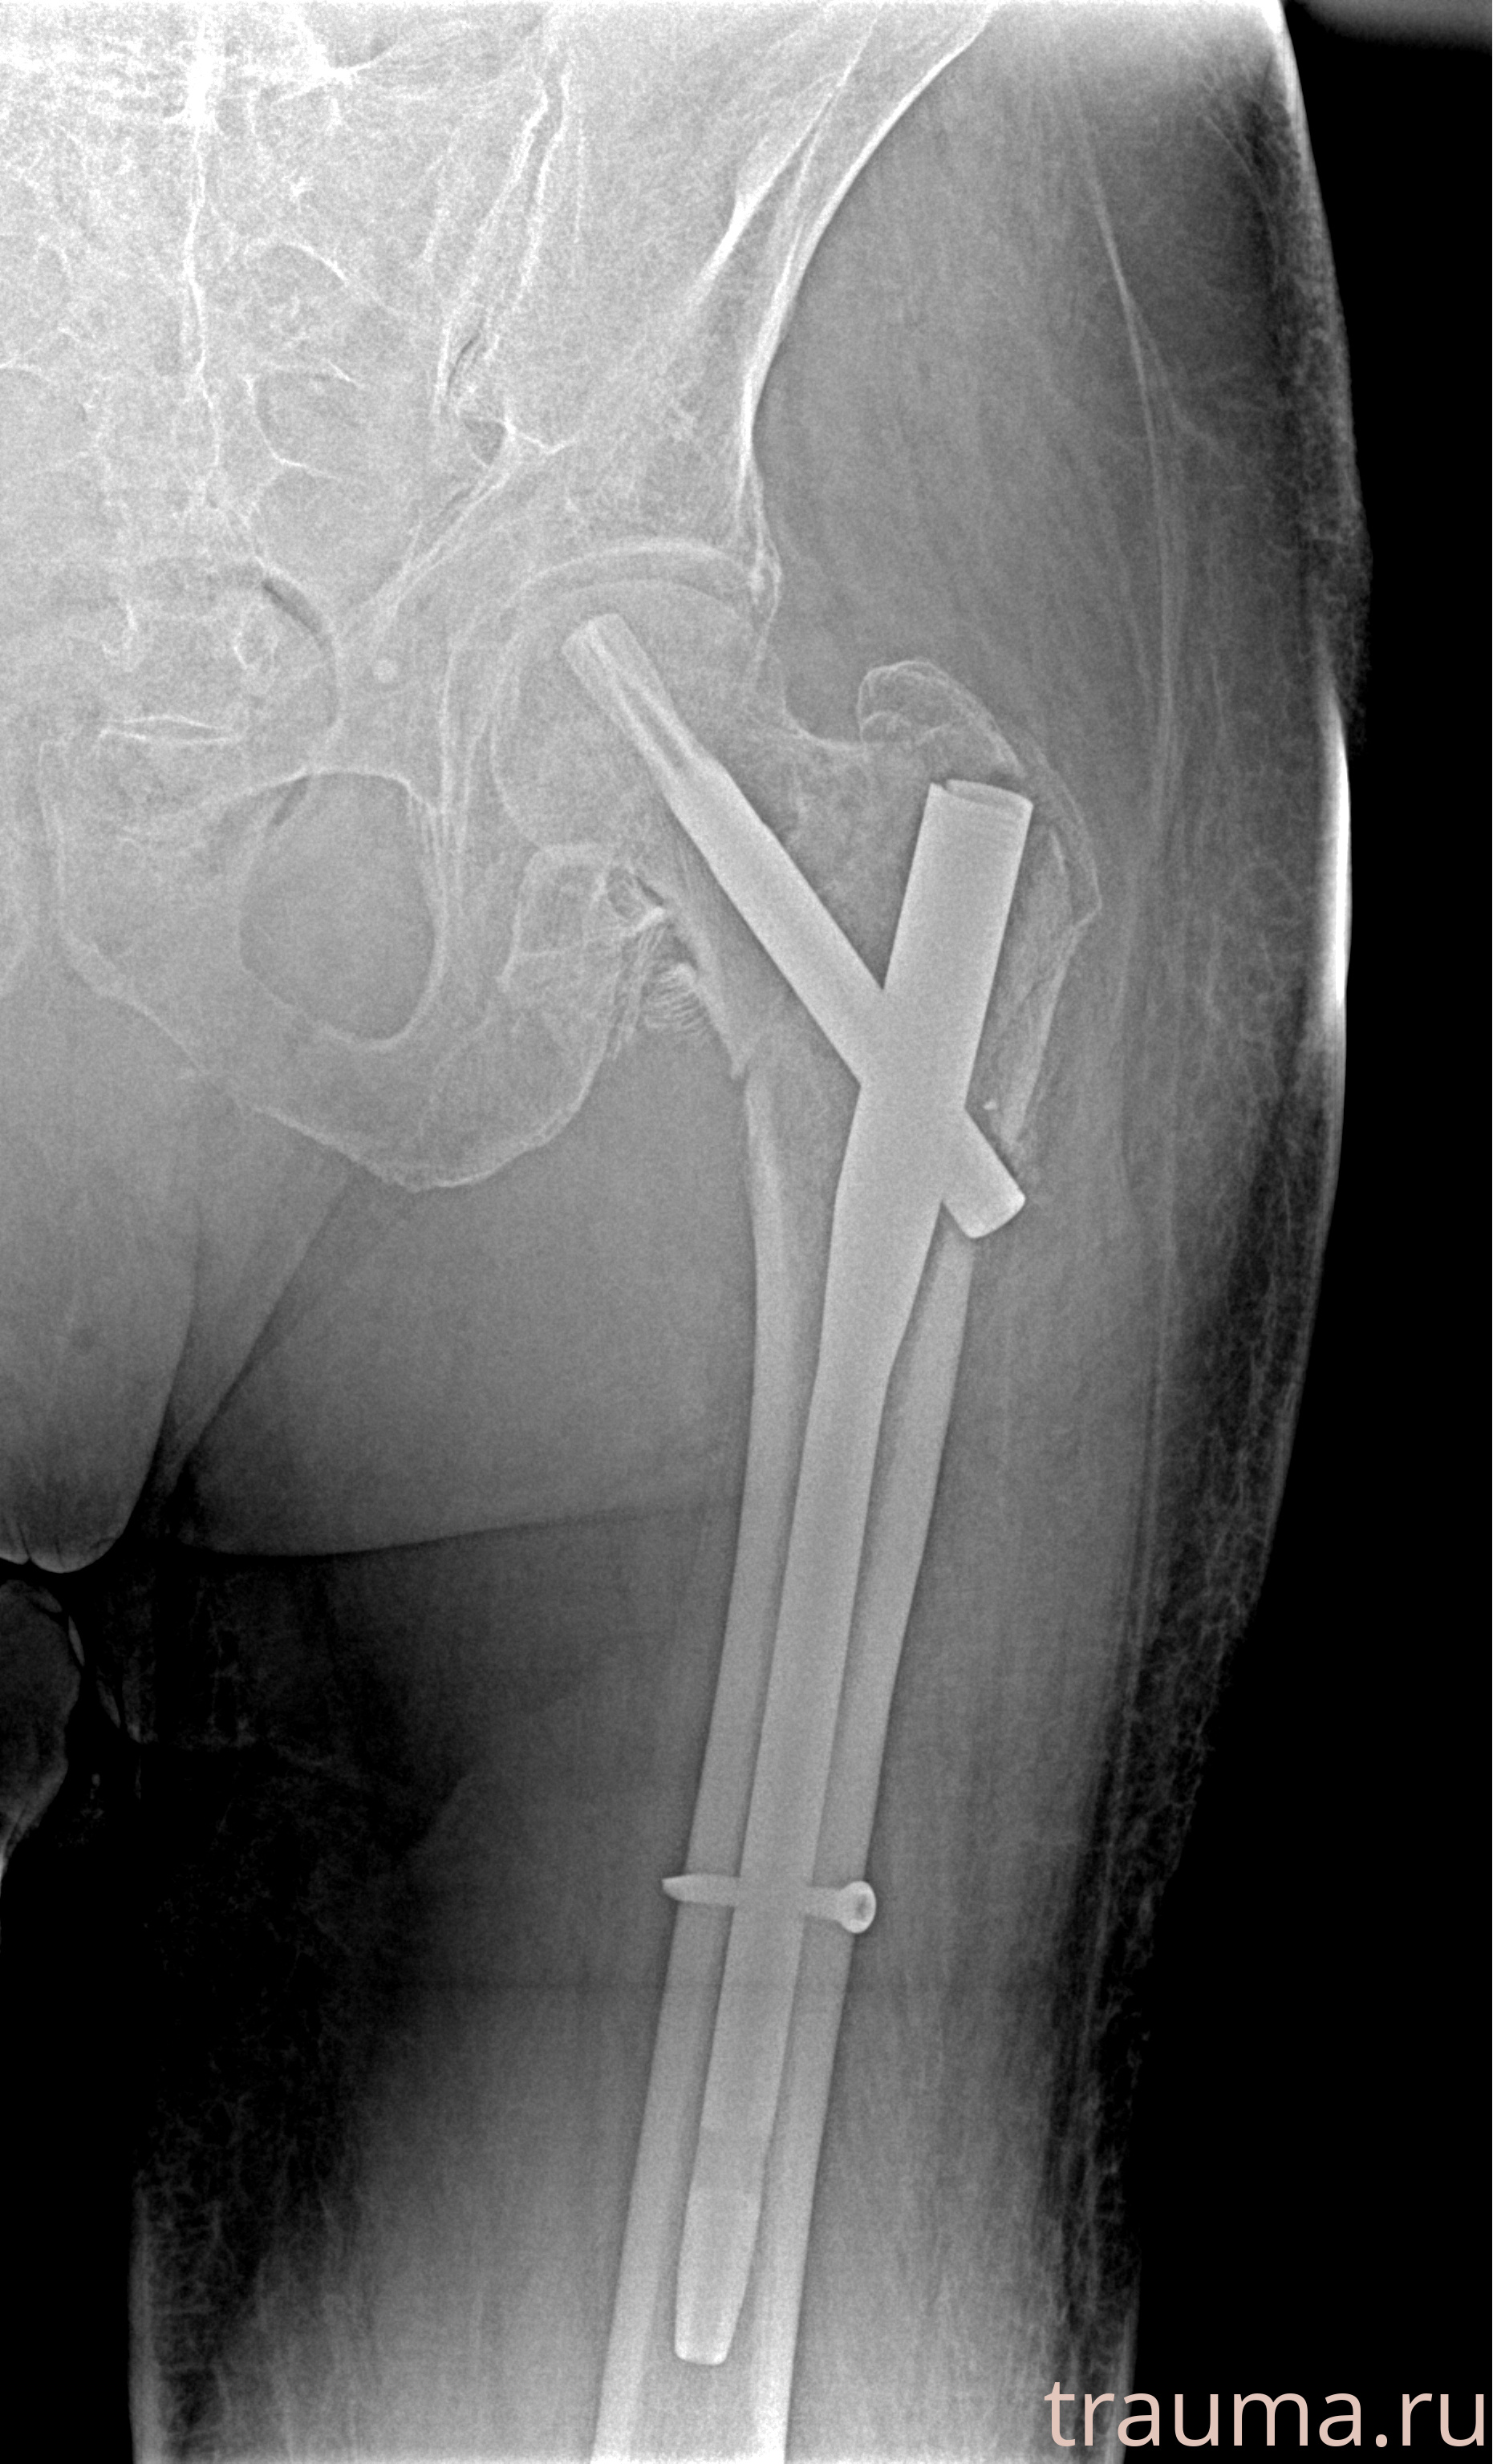

Рентгенограммы